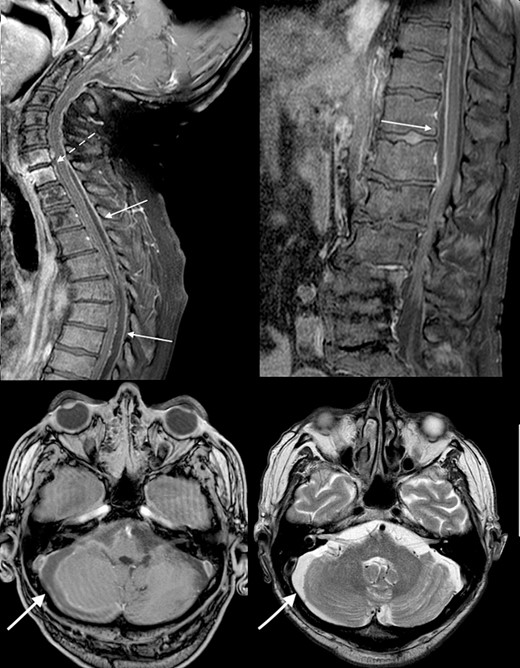

Urgent broad spectrum empiric antimicrobial therapy with Ceftriaxone, Metronidazole, and Vancomycin was initiated with guidance from Microbiology. Neurosurgical consultation advised MRI Brain and Whole Spine. In order to control the source of infection and obtain cultures and sensitivities, the TEP was removed under direct visualization (Fig. 2). A cuffed tracheostomy tube was inserted to prevent purulent discharge entering the trachea. MRI brain and whole spine revealed a vertebral C6-C7 osteomyelitis, subdural abscess, and epidural abscess within the spinal canal (Fig. 3). A recommendation for non-operative management with antimicrobial therapy was made by neurosurgery in light of the patient’s poor performance status and diffuse infection.

Clinical photograph of laryngectomy stoma and tracheoesophageal prosthesis.

Initial MRI brain and whole spine demonstrating vertebral C6-C7 osteomyelitis (dotted arrow), subdural abscess within the cerebellum (bold arrow), and an epidural abscess within the spinal canal (arrow).